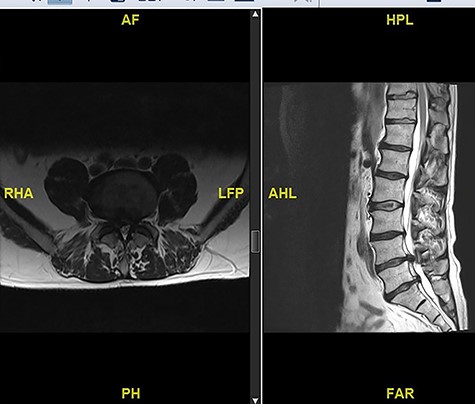

The updated MRI scan showed large disc prolapse at L4/5 level (Fig. 4) and the patient underwent emergency laminectomy/discectomy at L4/5. Post-operatively the patient’s pain improved however there still a retained loss of perineal sensation to pin-prick, a urinary catheter tug awareness was present and a good lower limb power was documented. The patient was discharged on the third post-operative day having been successfully mobilized and decatheterized with spontanous micturition.

The patient represented just over a month following the surgery to report about new onset weakness in the plantar flexion bilaterally, urinary incontinence, persistence of perineal sensation loss and new erection problems. There was no report of any pain and ambulation was still at ease. An MRI scan was organized a few days later (Fig. 5). The finding was deemed to be an IDH. Therefore, revision surgery followed the next day, with a durotomy and extraction of intradural disc fragments. As the patient had sphincter disturbance with neurogenic bladder and bowel difficulties, a referral to the regional spinal injury unit for aftercare as well as to the sexual dysfunction clinic for erection problems were organised.